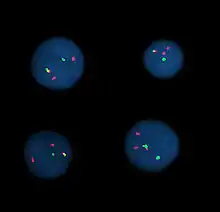

Fluorescence in situ hybridization

Fluorescence in situ hybridization (FISH) refers to using fluorescently labeled probe to hybridize to cytogenetic cell preparations.

The slide is aged using a salt solution usually consisting of 2X SSC (salt, sodium citrate). The slides are then dehydrated in ethanol, and the probe mixture is added. The sample DNA and the probe DNA are then co-denatured using a heated plate and allowed to re-anneal for at least 4 hours. The slides are then washed to remove the excess unbound probe, and counterstained with 4',6-Diamidino-2-phenylindole (DAPI) or propidium iodide.

Analysis

Analysis of FISH specimens is done by fluorescence microscopy by a clinical laboratory specialist in cytogenetics. For oncology, generally, a large number of interphase cells are scored in order to rule out low-level residual disease, generally between 200 and 1,000 cells are counted and scored. For congenital problems usually 20 metaphase cells are scored.